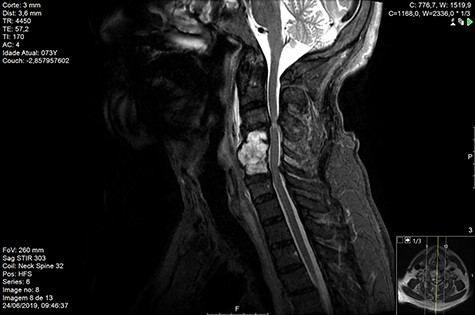

Computed tomography (CT) (Figs 1–3) and magnetic resonance imaging (MRI) (Figs 4–6) of the cervical spine were performed and revealed a lytic lesion involving most of C4, C5 and C6 vertebral bodies with bilateral extension to the posterior spinal elements of C4 and C5 and complete disruption of C4-C5 and C5-C6 intervertebral discs.

The Spinal Instability Neoplastic Score (SINS) [4, 6, 7] for assessing spinal instability from metastatic disease was used and the lesion was deemed unstable (SINS 13), with impending risk of increased neurological damage.

MRI and CT scans performed at 90 days post-radiation therapy showed an arrest of further progression of instability and resolution of the lytic lesion (Figs 7–13).